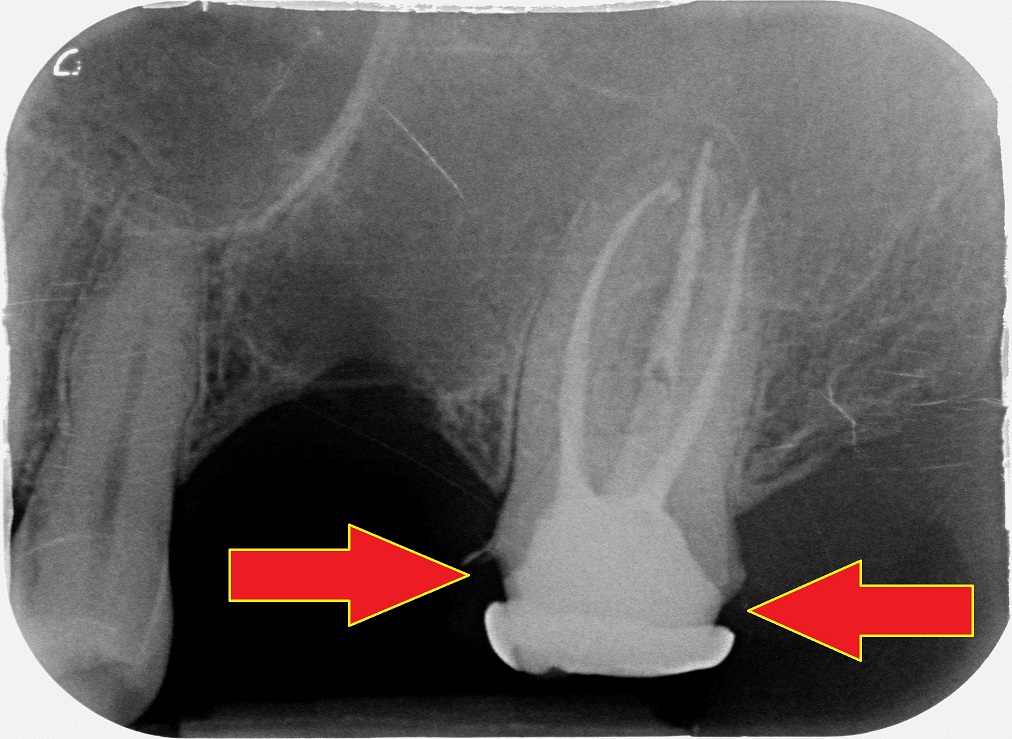

Questa signora ha appena finito questo lavoro da un dentista della mia zona che indovina un po’………rullo di tamburi …..tumturutumtuntum…….

NON E’ UN DENTISTA LOW COST!

So che la cosa ti sconvolgerà ma ti svelo la prima verità che ti ho promesso:

non è il low cost a svilire la professione ma

LA MANCANZA DI AGGIORNAMENTO.